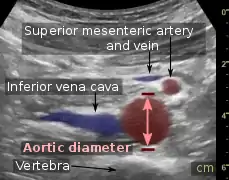

An abdominal aortic aneurysm is usually diagnosed by physical exam, abdominal ultrasound, or CT scan. Plain abdominal radiographs may show the outline of an aneurysm when its walls are calcified. However, the outline will be visible by X-ray in less than half of all aneurysms. Ultrasonography is used to screen for aneurysms and to determine their size if present. Additionally, free peritoneal fluid can be detected. It is noninvasive and sensitive, but the presence of bowel gas or obesity may limit its usefulness. CT scan has nearly 100% sensitivity for an aneurysm and is also useful in preoperative planning, detailing the anatomy and possibility for endovascular repair. In the case of suspected rupture, it can also reliably detect retroperitoneal fluid. Alternative less often used methods for visualization of an aneurysm include MRI and angiography.

Aortic measurement on abdominal ultrasonography in the axial plane between the outer margins of the aortic wall[37]

Aortic measurement on abdominal ultrasonography in the axial plane between the outer margins of the aortic wall[37] Ultrasonography in the sagittal plane, showing axial plane measure (dashed red line), as well as maximal diameter (dotted yellow line), which is preferred